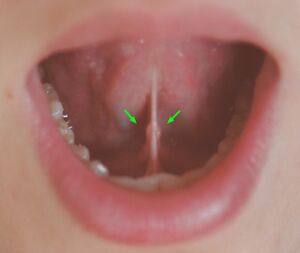

Submandibular gland papilla

The terminal part of the submandibular (Wharton's) duct is located in the mouth floor and opens as an orifice of the submandibular duct papilla. The position of the duct and its 0.5–1.5 mm wide ostium is invariably symmetric, but quite unpredictable; consequently, submandibular duct papilla can occasionally be challenging to recognize. Based on the macroscopic appearance of the papillae and sialendoscopic approach, Anicin et al. described four different types of submandibular gland papillae (types A, B, C, and D). [5]